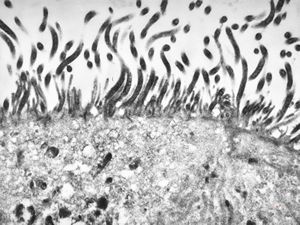

F,52y. | spirochetosis - colon

F,52y. | colon … spirochetosis … subepitheliai microbes